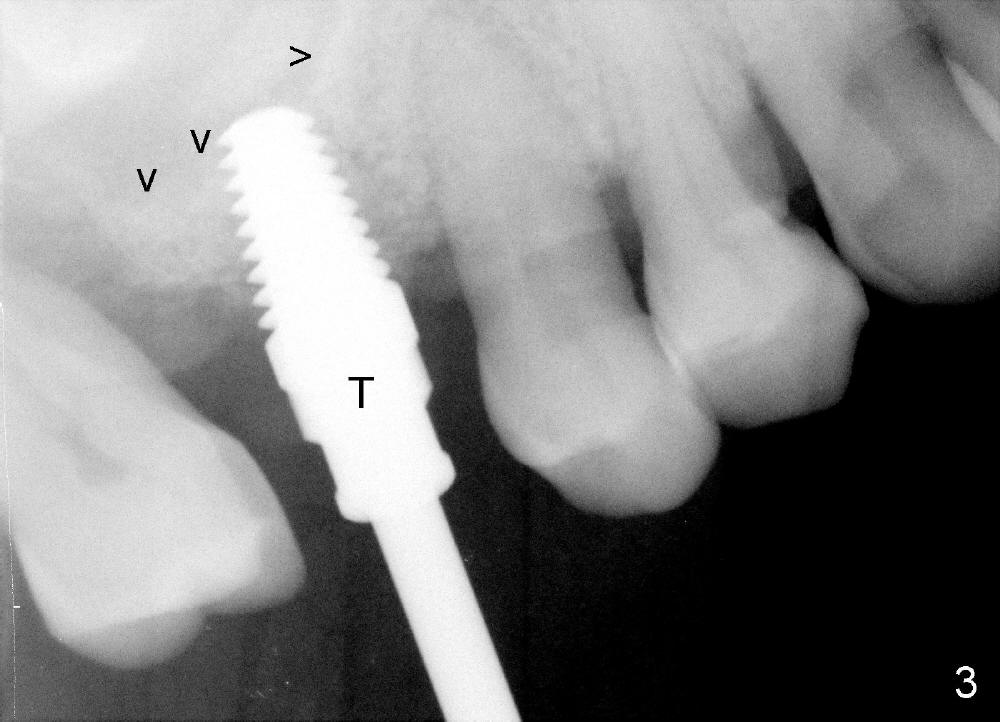

Bone expander kit is planned for for the case at the site of #3 with apparently normal buccolingual width (Fig.1). Bone density proves to be not low intraoperatively. First, when the 1.6 mm pilot drill is being used, the bone does not feel soft. Second, the first expander (2.6 mm, Fig.2 E) cannot be driven into the osteotomy (following the pilot drill) unless 2.5 mm reamer is used. Third, when larger expanders (until 3.8 mm) and 5x11 mm tap (Fig.3 T) are being used, the distobuccal plate starts to crack, although insertion torque of 5.3x8 mm implant is >50 Ncm (Fig.4). Using bone expanders is time consuming. In brief, when the buccolingual width is within normal limit and bone density is not low, traditional osteotomy should be adopted. It is better to use reamers to collect autogentous bone at the same time. The bone can be put back later into the osteotomy for sinus lift. Another drawback of this case is that the implant is not placed deep enough (Fig.5: 3 months postop). When a crown is cemented 1 year 4 months postop, the distal coronal portion of the implant is supragingival, although there is no infection.